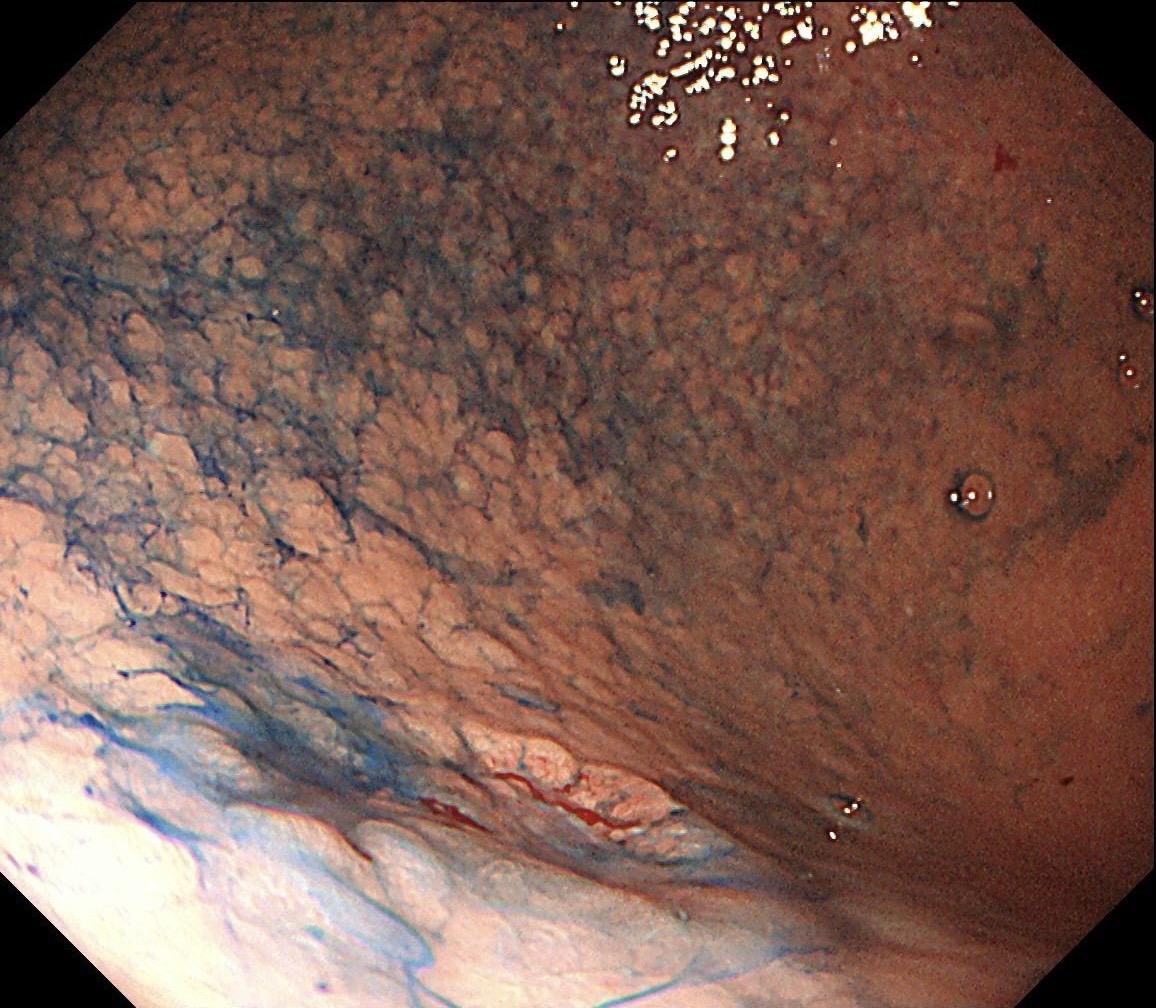

男,70岁,胃底体双发病变。看图猜猜病理呢……尤其胃底这个小的~凹陷性病变,当中央结构观察欠清时,边缘的异常微血管往往有提示作用,哪怕是局部。两处都考虑早期病变,拟ESD微创治疗。